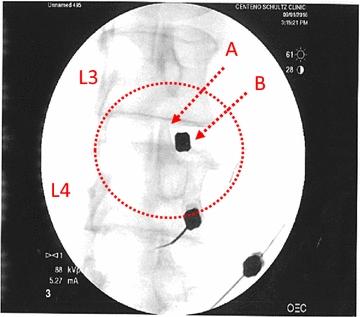

Thirty-three patients with lower back pain and disc degeneration with a posterior disc bulge diagnosed on magnetic resonance imaging (MRI) met the inclusion criteria and were treated with culture-expanded, autologous, bone marrow-derived MSCs. Prospective registry data was obtained at multiple time intervals up to 6 years post-treatment. Collected outcomes included numeric pain score (NPS), a modified single assessment numeric evaluation (SANE) rating, functional rating index (FRI), measurement of the intervertebral disc posterior dimension, and adverse events.

Three patients reported pain related to procedure that resolved. There were no serious adverse events (i.e. death, infection, or tumor) associated with the procedure. NPS change scores relative to baseline were significant at 3, 36, 48, 60, and 72 months post-treatment. The average modified SANE ratings showed a mean improvement of 60% at 3 years post-treatment. FRI post-treatment change score averages exceeded the minimal clinically important difference at all time points except 12 months. Twenty of the patients treated underwent post-treatment MRI and 85% had a reduction in disc bulge size, with an average reduction size of 23% post-treatment.

33 名患有下腰痛和椎间盘退变的患者,其磁共振成像(MRI)诊断为后椎间盘膨出,符合纳入标准,并接受了培养的、自体、骨髓来源的 MSCs 治疗。在治疗后 6 年的多个时间间隔内,前瞻性地获得了注册数据。收集的结果包括数字疼痛评分(NPS)、改良的单一评估数字评估(SANE)评分、功能评分指数(FRI)、椎间盘后径测量和不良事件。

3 名患者报告与手术相关的疼痛,但已缓解。与手术相关的严重不良事件(即死亡、感染或肿瘤)无发生。与基线相比,治疗后 3、36、48、60 和 72 个月时 NPS 变化评分均有显著差异。治疗后 3 年平均改良 SANE 评分显示 60%的平均改善。除 12 个月外,FRI 治疗后变化评分平均值均超过最小临床重要差异。20 名接受治疗的患者接受了治疗后的 MRI,85%的患者椎间盘膨出尺寸减小,治疗后平均减小 23%。